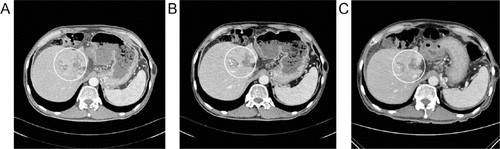

환자에게 중대한 합병증 없이 고주파온열치료가 32회 실시되었다치료 중 탄수화물 항원 19-9(CA 19-9)와 총 빌리루빈 수치가 감소했다(그림 1  2). 환자의 ECOG8 등급은 3점에서 2점으로 개선되었다피로, 소화 불량, 상복부 통증 및 황달 등 여러 증상이 감소했다국립 암 연구소 부작용에 대한 공통 용어 기준(NCI-CTCAE) 4.0 버전에 따르면 피로감은 3등급에서 1등급으로 개선되고 소화 불량은 2등급에서 1등급으로 개선되었다. 고온 요법과 화학 요법 병용 중 종양의 크기를 CT 스캔을 이용하여 측정하였고, 종양에 어떤 진행도 관찰되지 않았다(그림 3). 이와 같이 우리는 고체 종양의 반응 평가 기준(RECIST) 버전 1.1에 따라 질병이 안정되는 것을 확인했다.10

그림 3. CT 스캔 이미지화학 요법과 고주파온열치료 병용 치료 중 종양의 크기는 9(A), 11(B), 12(C) 2016 CT 스캔을 사용하여 측정되었다. 종양의 진행은 관찰되지 않았다.